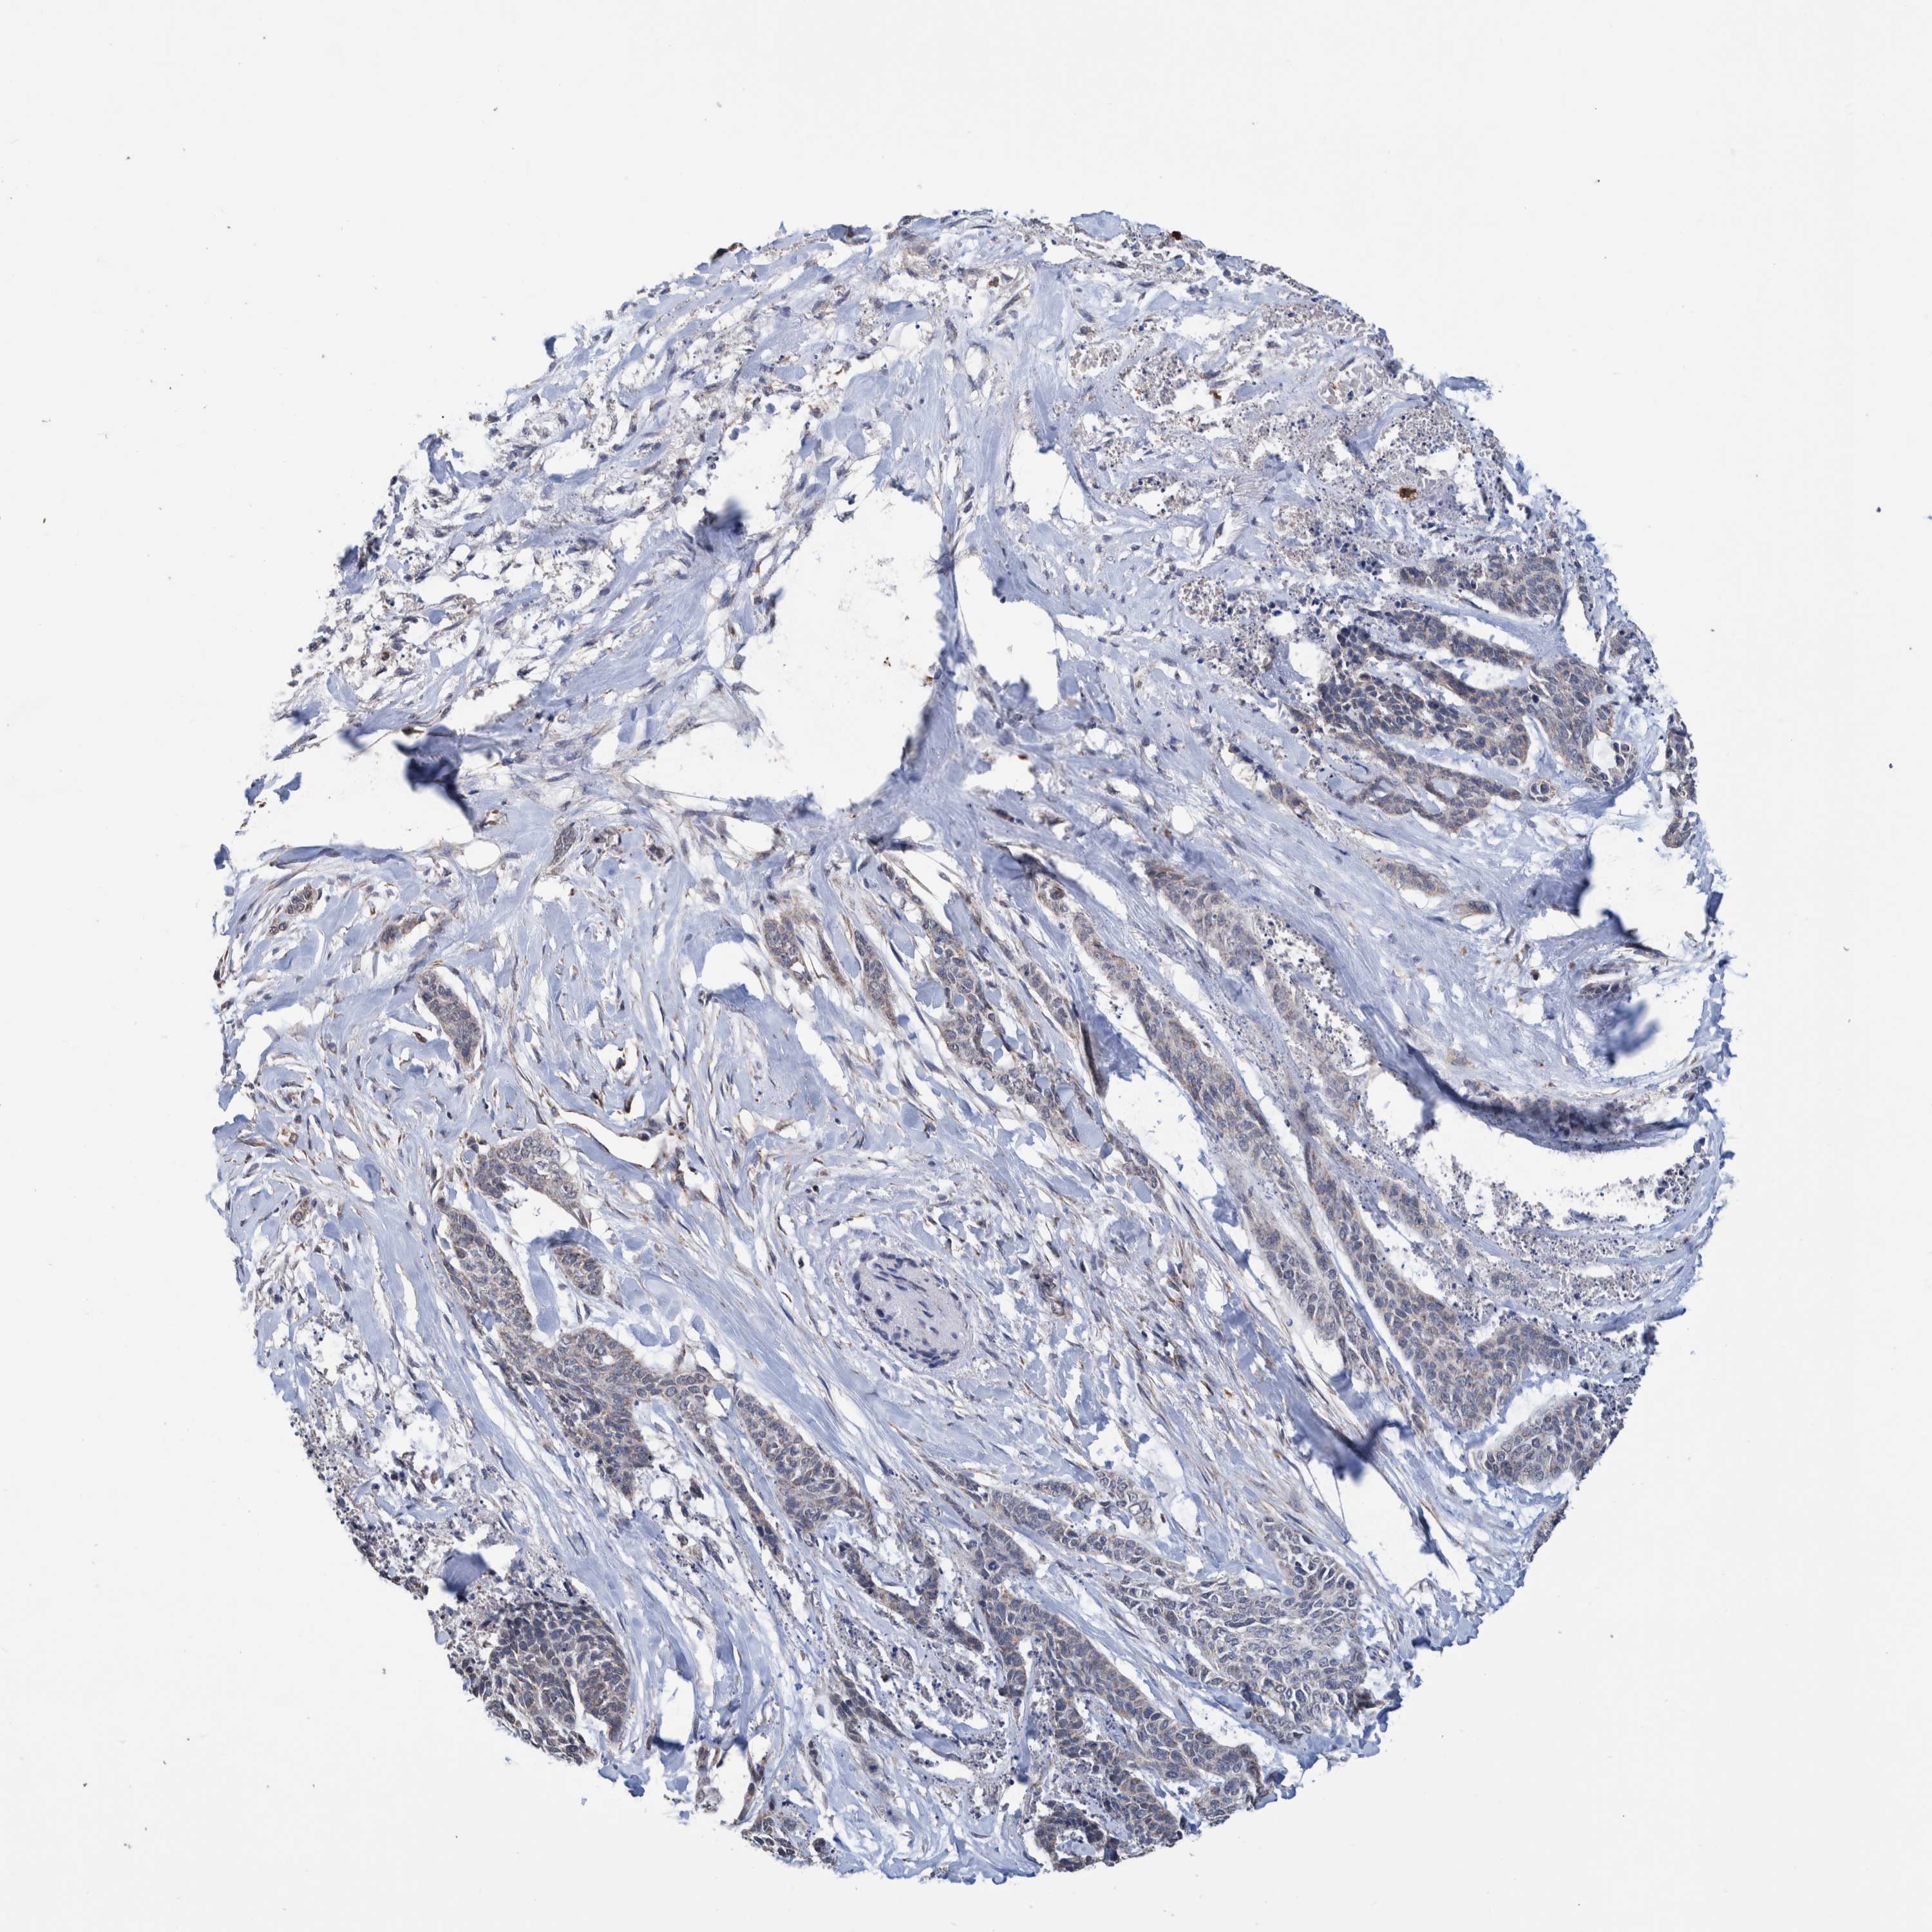

SKIN CANCER - Protein expressioni

A mouse-over function shows sample information and annotation data. Click on an image to view it in a full screen mode. Samples can be filtered based on level of antibody staining by selecting one or several of the following categories: high, medium, low and not detected. The assay and annotation is described here.

Each image is clickable and will lead to virtual microscopy that enables deeper exploration of all samples and also displays staining intensity scores, fraction scores and subcellular localization as well as patient and tissue information for each sample.

Antibody HPA023238

Squamous cell carcinoma, metastatic, NOS

Squamous cell carcinoma, NOS